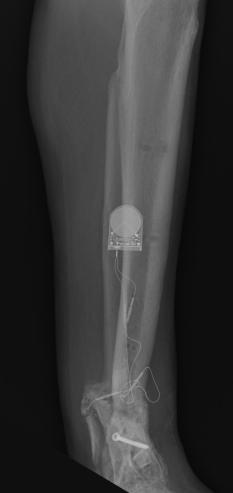

Postoperative (12th) images of left ankle

The images displayed here were created at various appointments following surgery performed by Dr. Daniel Saunders. In the X-Ray you can see

where Dr. Saunders has removed the fibula plate, joined the tibia and fibula with a screw, built-up the area of the tibia where previously

there was considerable absence of bone and lastly added the EBI OsteoGen-M Bone Stimulator (dual lead). The photos show the left side site

where the fibula plate was removed, the top site where donor bone, bone filler material and the stimulator were added and the right side

where the tissue has burst because of swelling. Liam was placed on an IV drip of Vancomycin following surgery to combat the potential onset

of Osteomyelitis. The image of the cast includes the fibula plate that was removed during surgery. The next images were taken later and show

that the staples and stitches were removed. In one of the images, you can see Liam's wife Madeline helping with leg cleanup and in one image

can be seen the EBI representative after being put to work (holding up the left leg while the latest cast cures) by Dr. Saunders. Later shots show

a healing tissue burst site with some overgrowth and Dr. Saunders cauterizing the overgrowth. Bones shifting too much (shown in X-Rays). The

last images are of the left ankle prior to the 13th surgery.